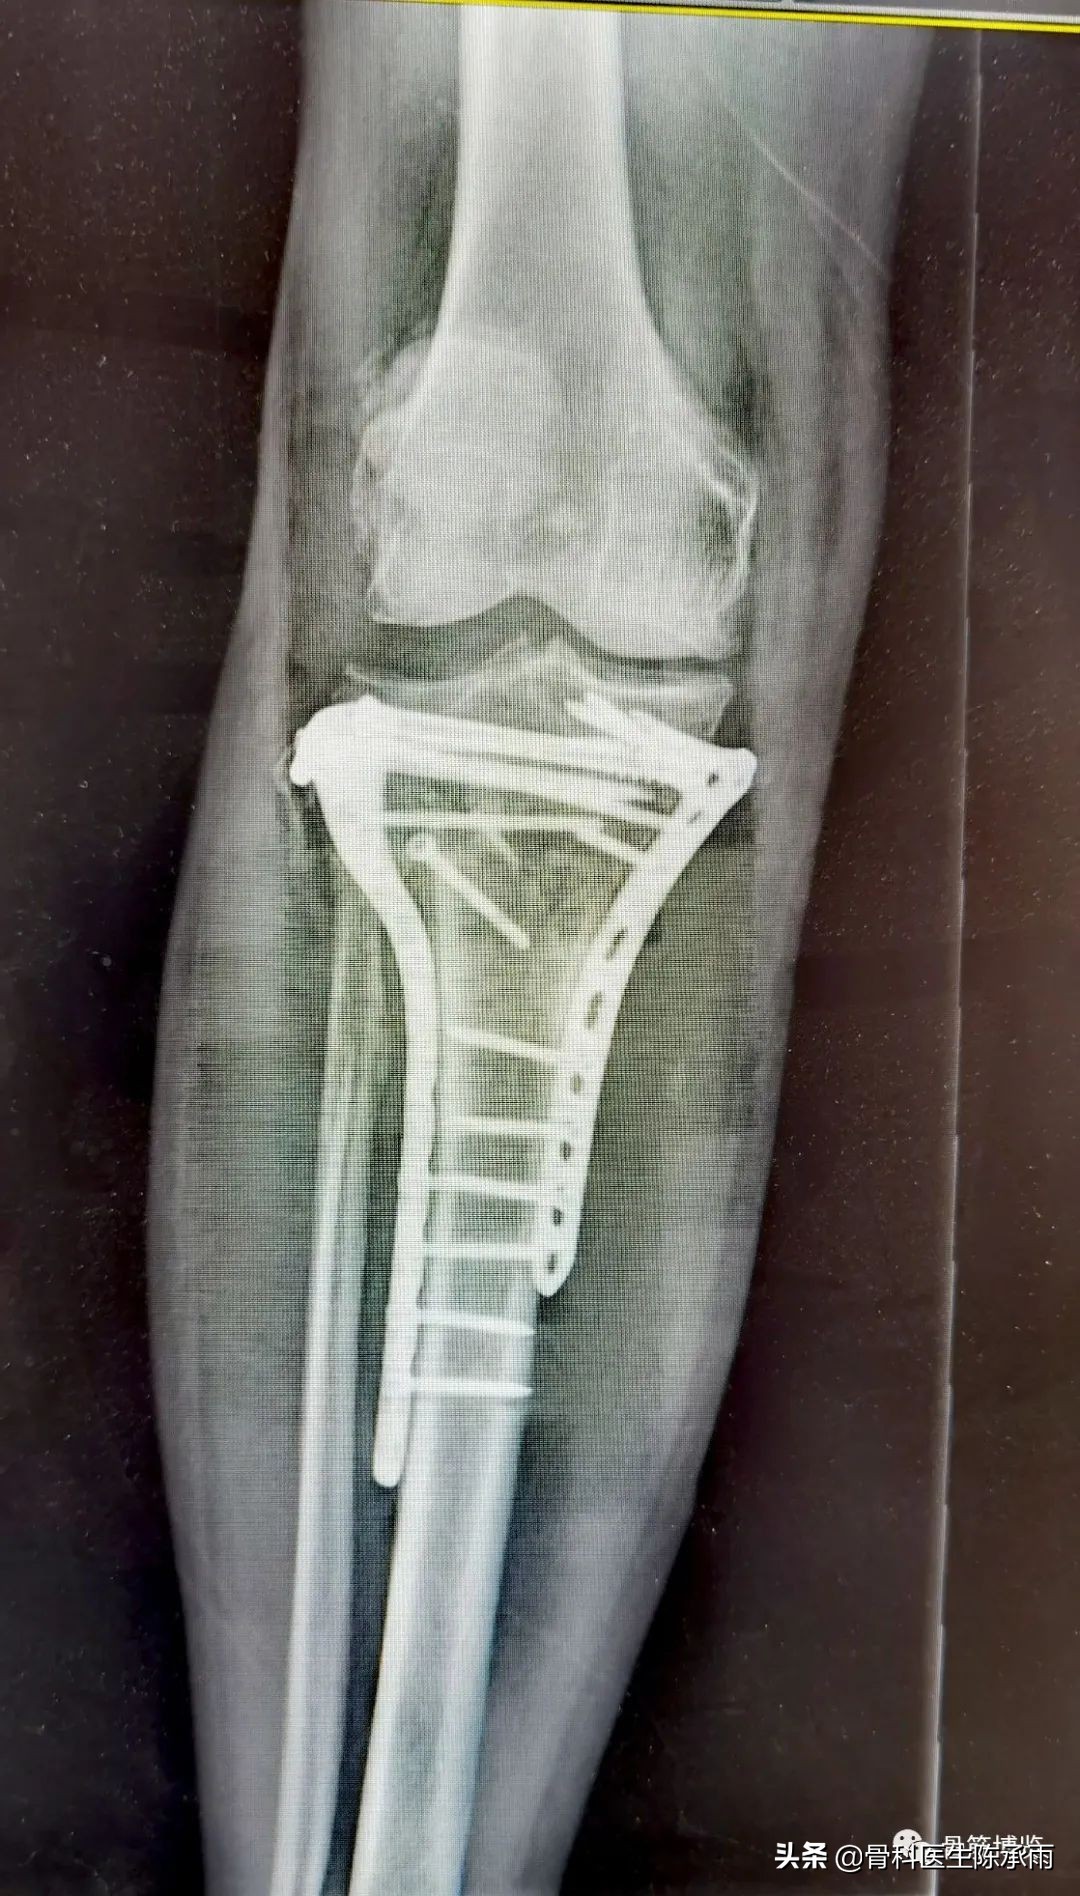

下例胫平台骨折皮肤条件差,内侧板取两端小切口置入内板固定。胫骨结节处撕脱骨折以1枚拉力螺钉固定。